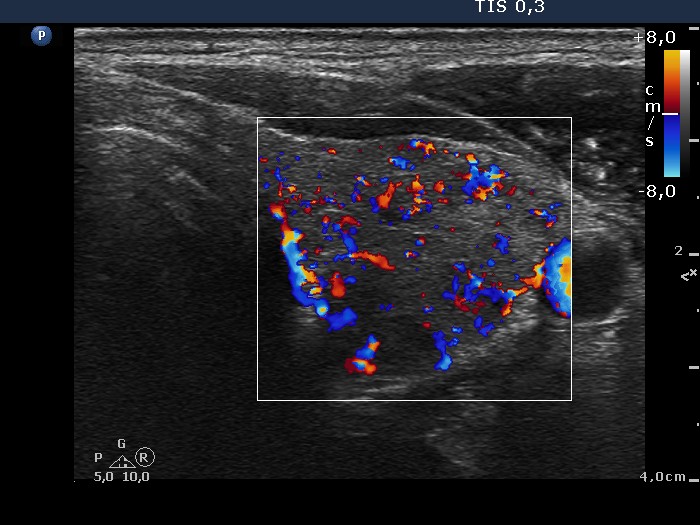

Ultrasonography: the thyroid was composed of minimally and moderately hypoechogenic and echonormal areas. None of the lesions fit to a nodule. The vascularization was moderately increased.